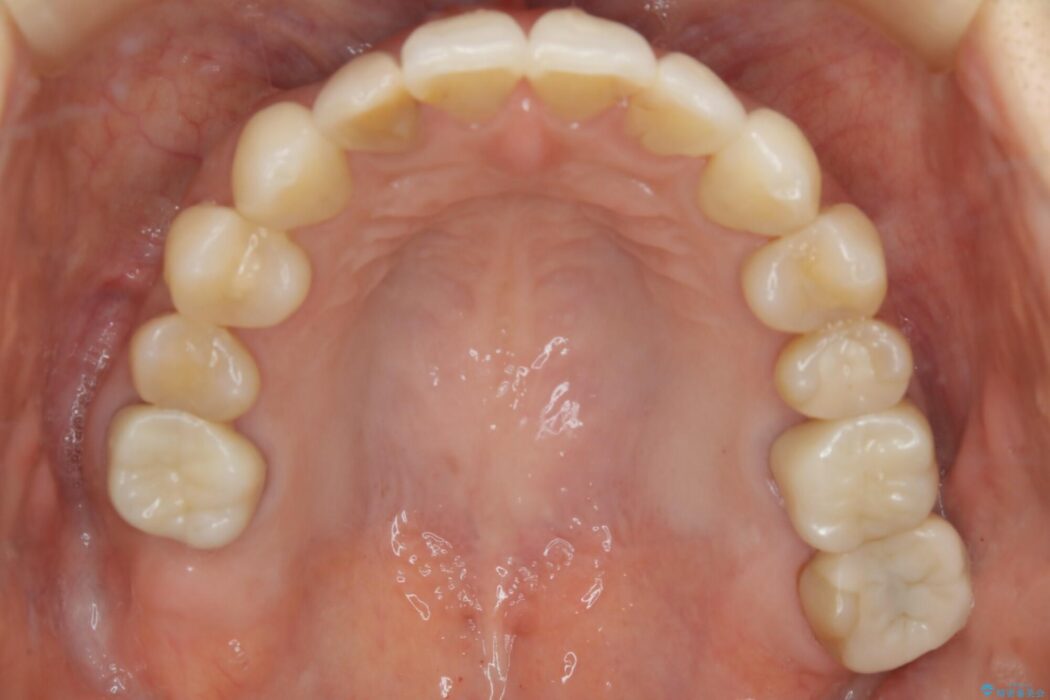

全体的に歯列が狭窄しており、本来外側に覆いかぶさっている上の前歯が内側に入り込んでいました。

歯列弓全体の形状を整えるとともに歯の大きさもコントロールすることで非抜歯にて矯正を行いました。

歯列弓の拡大

歯並びが悪くなる原因の一つに「歯列弓の狭窄」というものがあります。

奥歯や前歯が内側(舌側)に倒れ込んでしまったり、歯が生えてくる位置が内側になってしまうことにより歯並びのアーチが狭くなってしまうことを言います。

このような場合、歯並びのアーチを拡大してあげるだけでもガタつきを無くすためのスペースがかなり作れることがあります。